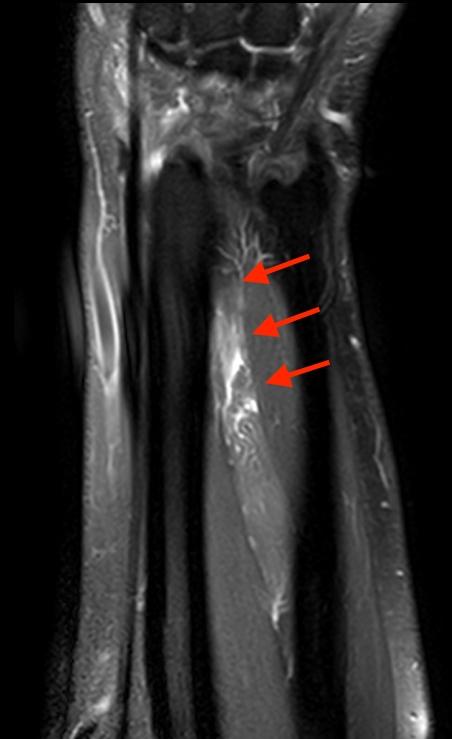

The long extensor tendon to the thumb is called the extensor pollicis longus (epl). Extensor Pollicis Longus Rupture

Extensor Pollicis Longus Rupture from radsource.us

Its muscle belly is in the forearm and the tendon travels along the wrist and enters the third compartment of the band that holds the tendons in position at the wrist. The epl straightens the most distal (farthest from your body) joint of the thumb. The long extensor tendon to the thumb is called the extensor pollicis longus (epl). Often, the two ends of the tendon are very damaged and cannot be sewn back together. Apb (pulley around ulnar side of wrist) high median nerve palsy. This tendon straightens the end joint of the thumb and also helps pull the thumb in towards the index finger. Jun 24, 2021 · eip to epl tendon transfer. What is the epl tendon?

The tendon runs around a bony prominence on the back of the wrist called lister’s tubercle.

Its muscle belly is in the forearm and the tendon travels along the wrist and enters the third compartment of the band that holds the tendons in position at the wrist. 2 weeks ago espn's adam schefter is reporting that cleveland browns right tackle jack conklin (knee) is feared to have torn his patella tendon during week 12's loss to the baltimore ravens. The long extensor tendon to the thumb is called the extensor pollicis longus (epl). What is the epl tendon? This tendon straightens the end joint of the thumb and also helps pull the thumb in towards the index finger.